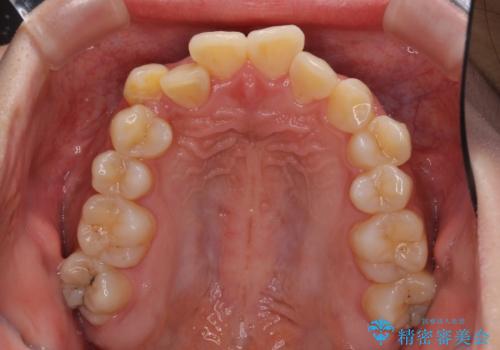

- 八重歯やデコボコをインビザラインで治療したいとのことで来院された患者様です。

インビザライン単体で治療を行うには叢生が強いと判断されたため、事前にワイヤー装置で抜歯矯正を行い、ある程度改善してからインビザラインにて仕上げていくこととしました。